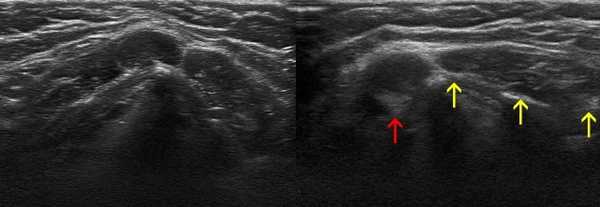

- Метастатический узел: гипоэхогенный, округлый ± некроз, отсутствие ворот, периферическая сосудистая сеть

- Туберкулезный узел: интранодальный некроз, матирование, отек мягких тканей, смещенная сосудистая сеть или аваскулярный вид

- Метастатический узел от папиллярного рака щитовидной железы: гиперэхогенный, узловой некроз, точечная кальцификация

- Лимфоузлы неходжкинской лимфомы: сплошное, гипоэхогенное, округлое, псевдокистозное / сетчатое эхообразование, выраженная внутригрудная и периферическая сосудистая сеть

- Метастатический узел. Увеличенный, округлый, гипоэхогенный лимфатический узел. Обычно солидный, но может показать интранодальный кистозный некроз (плоскоклеточный рак, папиллярный рак щитовидной железы). Отсутствуют эхогенные ворота. Периферическая сосудистая сеть и RI> 0,8, PI> 1,6

- Туберкулезный лимфоузел. Круглый, гипоэхогенный, интранодальный некроз. Комковатое / узловое матирование с отсутствием нормальных мягких тканей между узлами. Отек мягких тканей ± целлюлит ± абсцесс. Цветовой допплер: смещенная хиларная сосудистая сеть или аваскулярная структура

- Метастатический узел от папиллярной карциномы щитовидной железы. Гиперэхогенный (характерный) ± интранодальный некроз. Точечная кальцификация, представляющая тела псаммомы. Цветовой допплер: повышенная хаотичность периферических сосудов, переменное внутрисосудистое сопротивление

- Неходжкинский лимфомный узел. Множественные цепи включали ± увеличенные лимфатические узлы в остальной части тела. Сплошной, гипоэхогенный, округлый, псевдокистный / сетчатый эхо. Отмечается внутриузловая и периферическая сосудистая сеть. Хиларный кровоток более выраженный, чем периферический